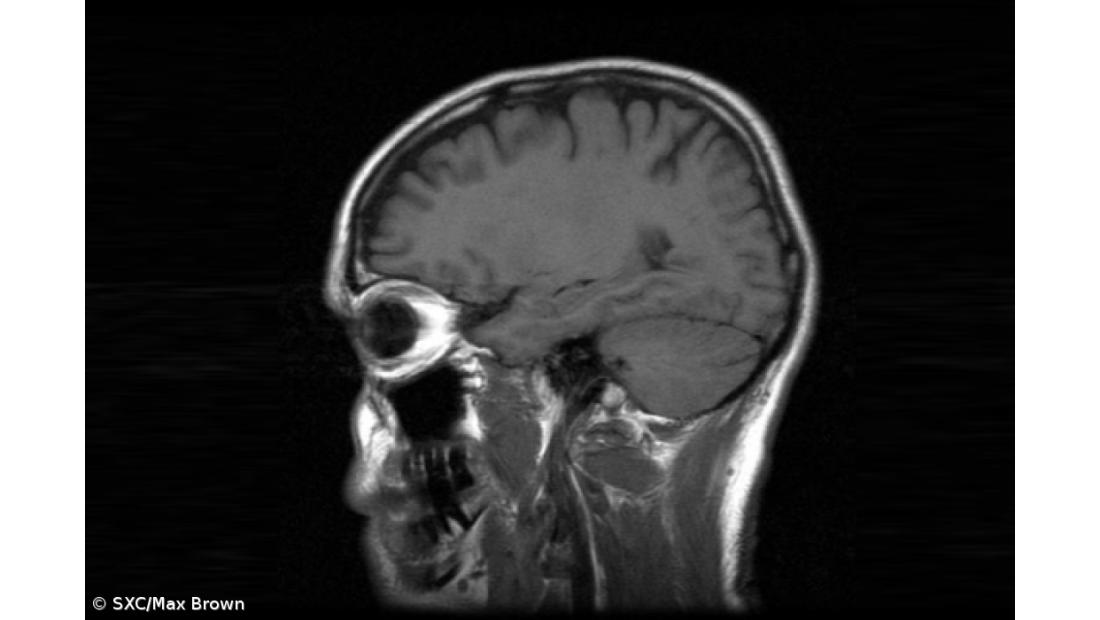

A maioria dos animais tem corpos com simetria espelhada (esquerda e direita são iguais, mas invertidas), propriedade que o cérebro partilha, exceto no caso de algumas funções cognitivas que parecem lateralizadas.

Até ao momento, os mecanismos biológicos que fazem com que essa simetria no cérebro desapareça, em alguns casos, não são bem compreendidos.

O investigador do Conselho Superior de Investigação Científica (CSIC), em Espanha, Luis Seoane, desenvolveu uma nova teoria matemática que demonstra como o aparecimento de mais complexidade cognitiva acarreta uma pressão evolutiva que favorece a lateralização cerebral.